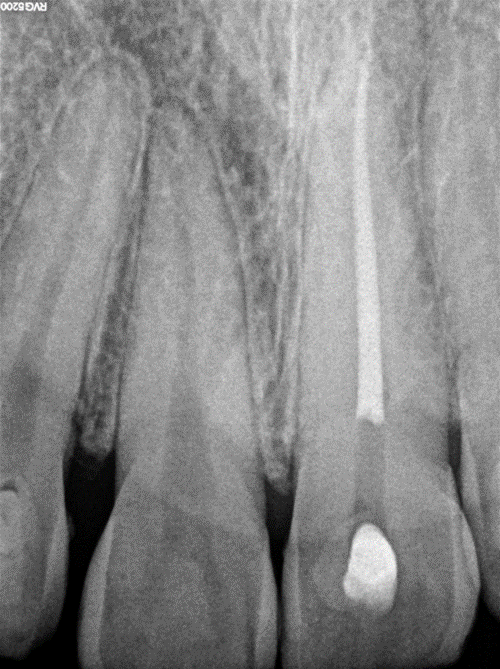

This tooth did not respond neither for thermal nor electric pulp testing. Root canal treatment was initiated in tooth #21 with the aid of Endo access bur and following the measurements and angulations taken from the cone beam computed tomography (CBCT). The canal was located by the aid of a dental operating microscope and negotiated with a size #10 C file. The preparation of the root canal system was done by Reciproc files, 5.25% sodium hypochlorite, and 17% EDTA. Obturation was done with gutta percha and EndoSequence® BC Sealer (hydraulic condensation technique). Internal bleaching (non-vital walking bleaching) was initiated using Opalescence™ Endo. following the manufacturer’s instructions. Opalescence Endo bleaching gel was administered into the coronal pulp chamber while ensuring it does not come into contact with soft tissues. Temporary filling was placed, and made sure that there was sufficient occlusal clearance (Figure 3). After 5 days, the desired change in tooth color was achieved. Then, both the provisional restorative material and the bleaching material were removed until the level of coronal sealing material. Seal the access opening using a preferred barrier and temporary restorative materials. Wait a period of 7–10 days following the whitening procedures before proceeding with the placement of a permanent restoration, as whitening materials can interfere with the bonding agents used in restorative procedures. Then, permanent composite restoration was placed to seal the palatal access cavity in tooth #21. By the end of this step, part of the patient’s chief complaint was addressed by bleaching the tooth internally and matching the adjacent teeth' color. However, White spot lesions are going to be in the following step by applying the ICON resin infiltration following the manufacturer’s instructions.

Figure 3. Periapical radiograph showing tooth #21 after root canal treatment.